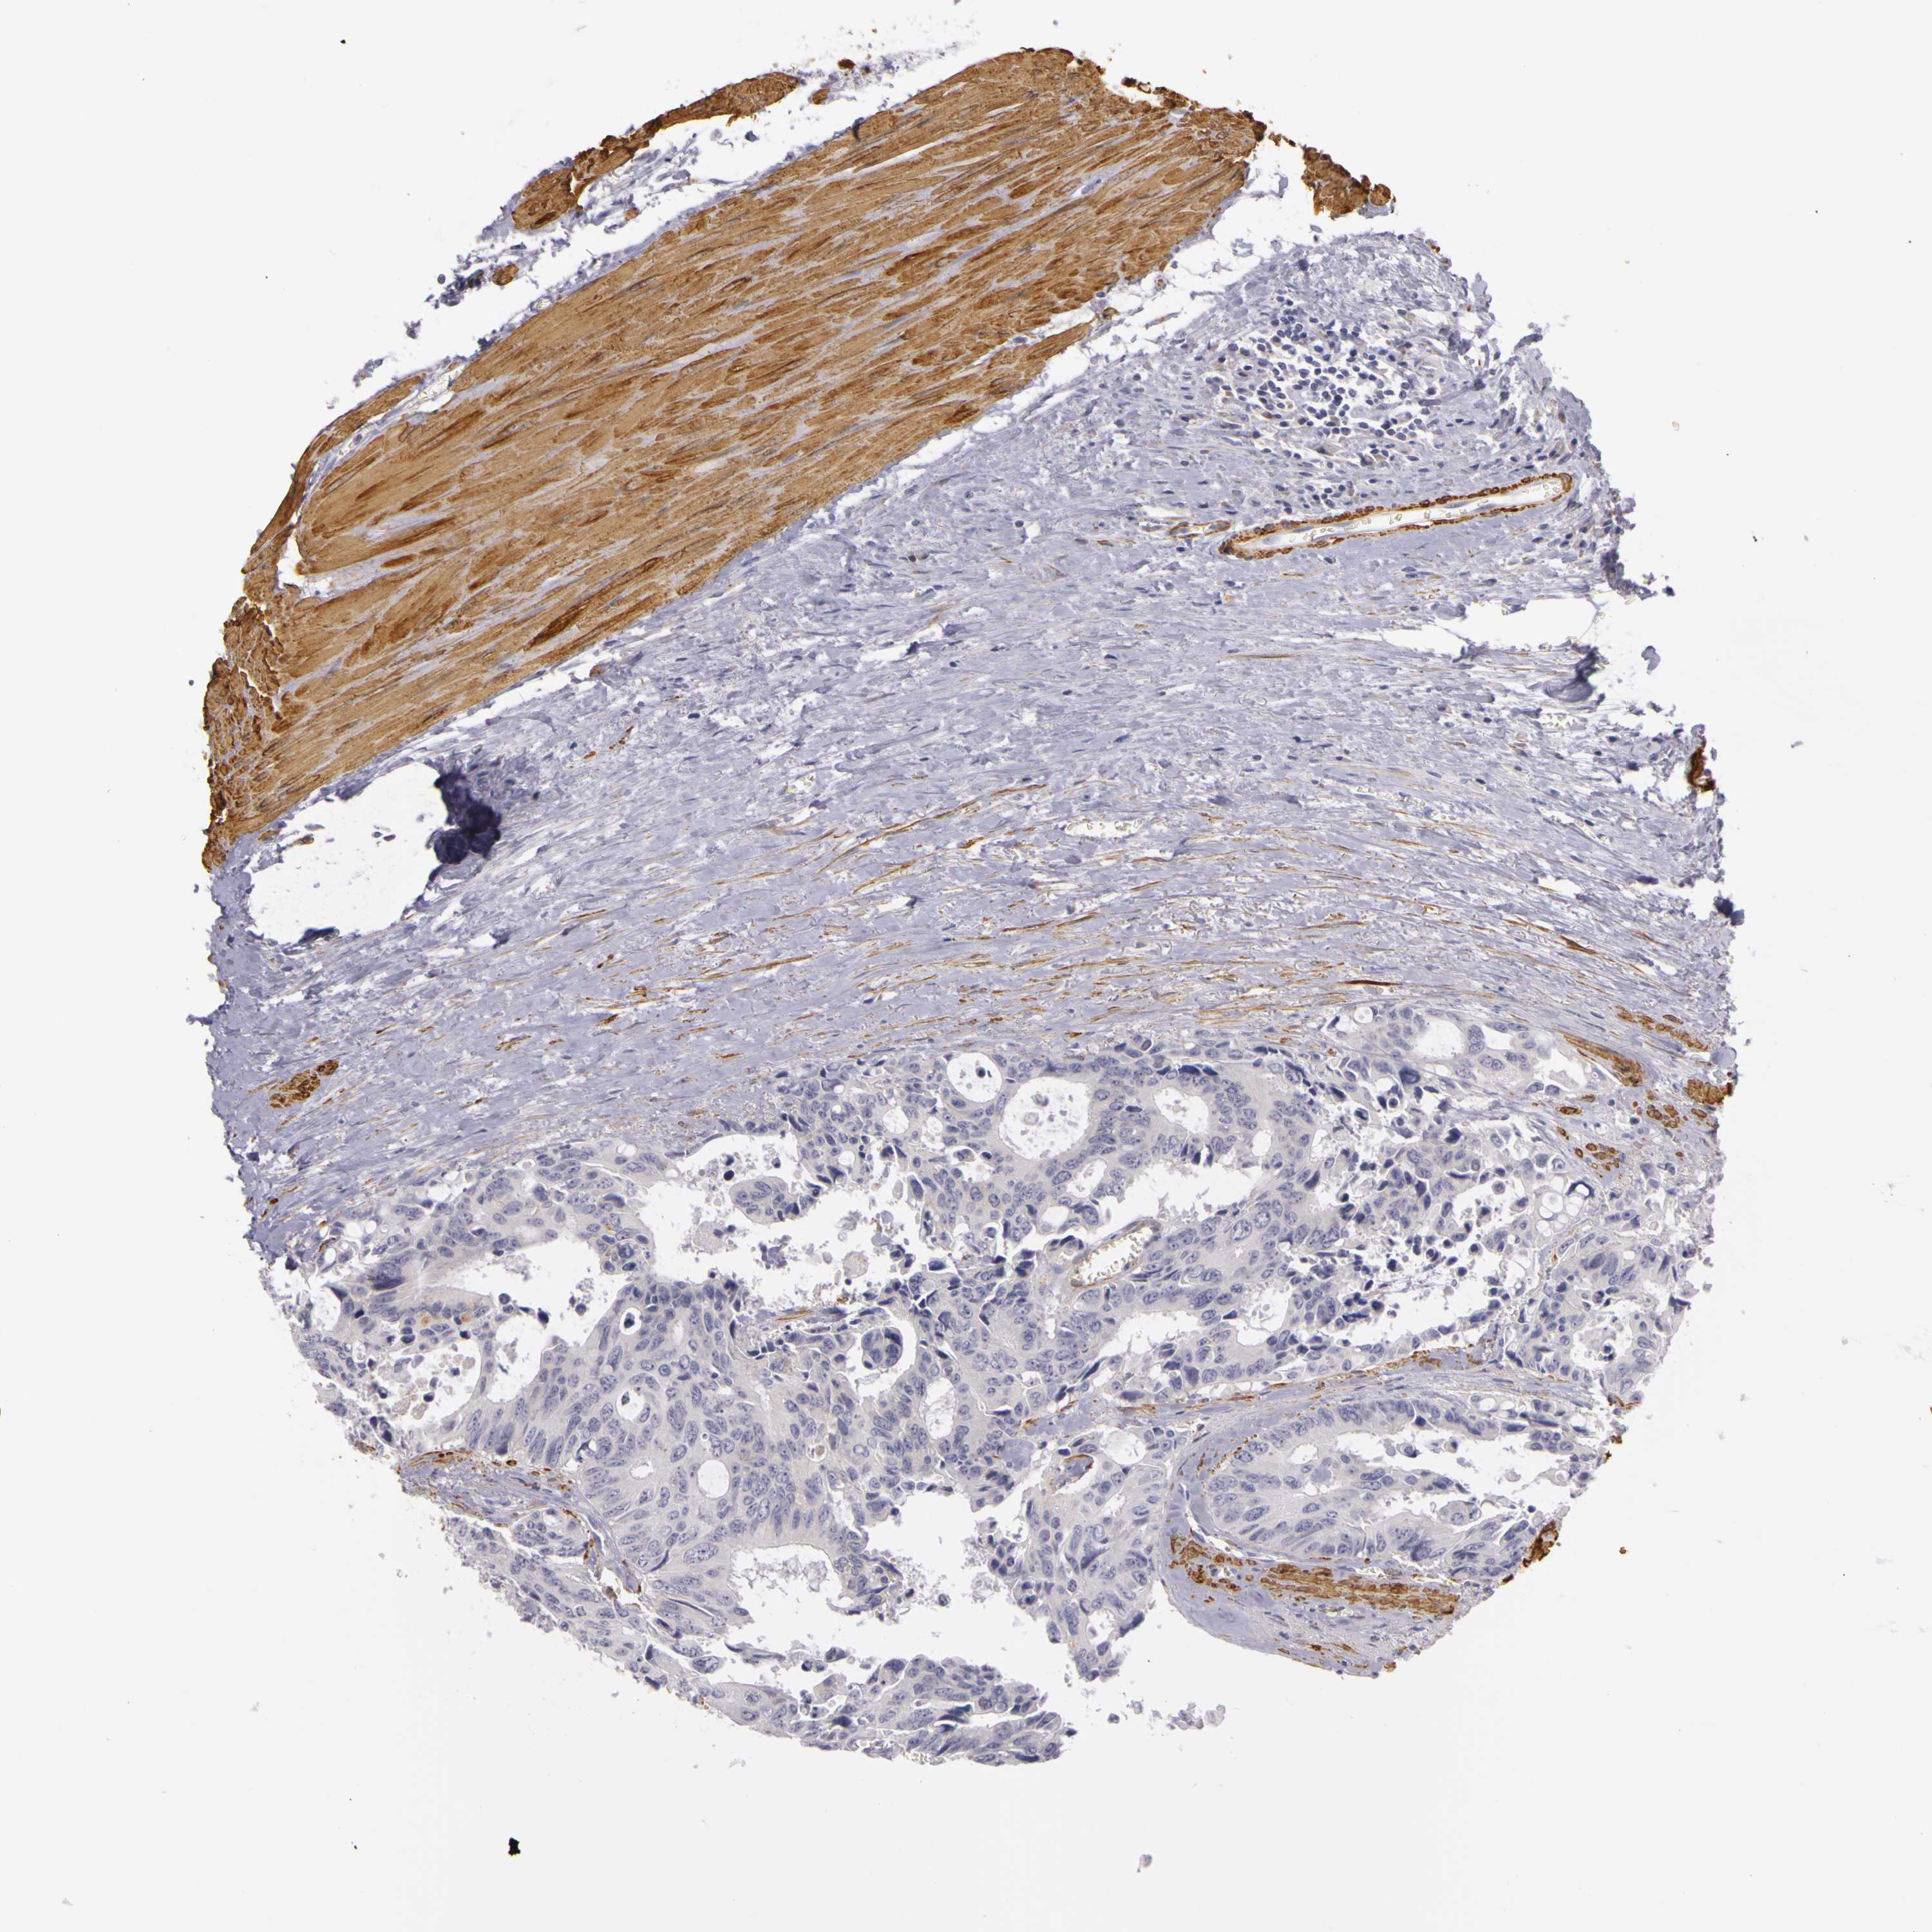

CANCER COLORECTAL CANCER Show tissue menu

Colorectal cancer

Human cancer

Colon adenocarcinoma